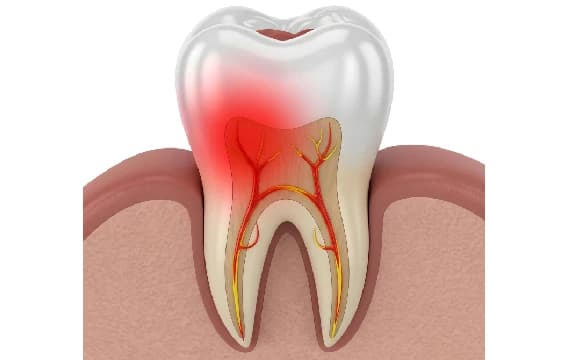

Root canal treatment